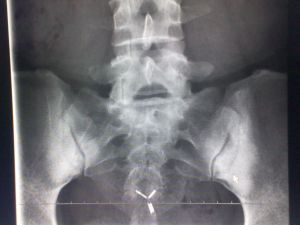

X線檢查:病變在骶髂關節的骼骨耳狀面上出現骨質呈均勻性密度增高,骨小梁消失,邊緣模糊,不侵犯關節面,病變寬度約0.5~3.0厘米,濃白實密徵象。其骨質硬化區構成各種不同的形態,大體上分為三角形、新月形、梨形三種。

X線所見:骶髂關節正位片見關節間隙整齊清晰,靠近骶髂關節面中下2/3的髂骨側骨質異常緻密呈均勻一致的骨質緻密帶,骨小梁紋理完全消失,邊緣清晰但無骨質破壞,不侵犯骶骨側。這種病變多為對稱性,也可發生於單側。局部可呈三角形,新月形或梨形。硬化區可寬達3cm。